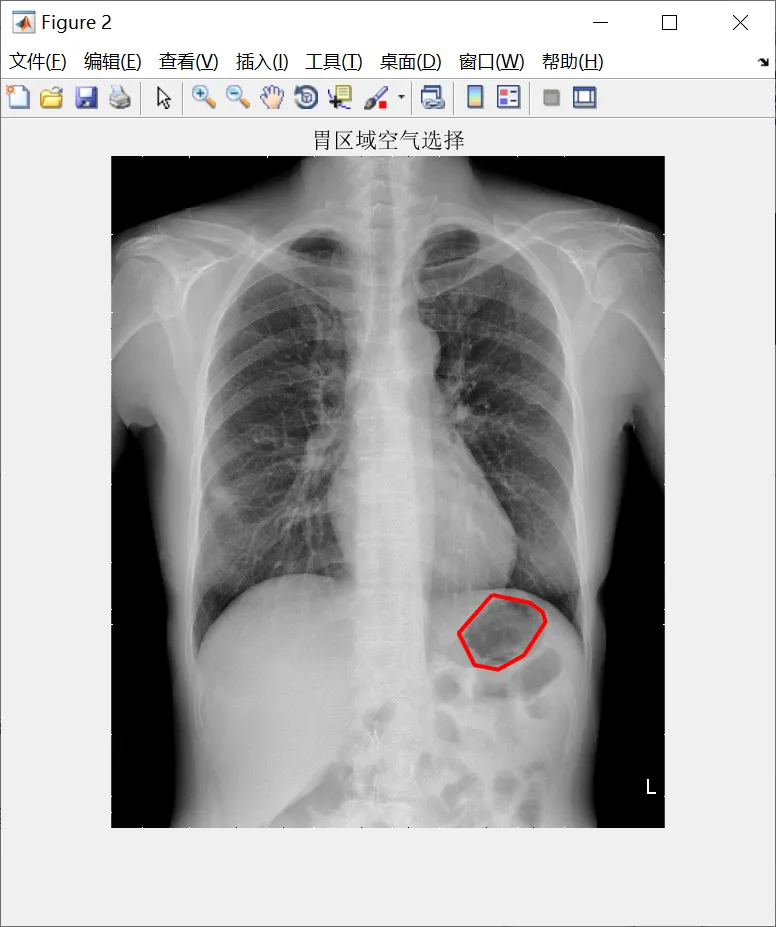

% 圈选胃区域空气

c = [1524 1390 1454 1548 1652 1738 1725 1673 1524];

r = [1756 1909 2037 2055 1997 1863 1824 1787 1756];

bw_poly = roipoly(bw_direct, c, r);

figure;

imshow(I, []);

hold on;

plot(c, r, 'r-', 'LineWidth', 2);

hold off;

title('胃区域空气选择');